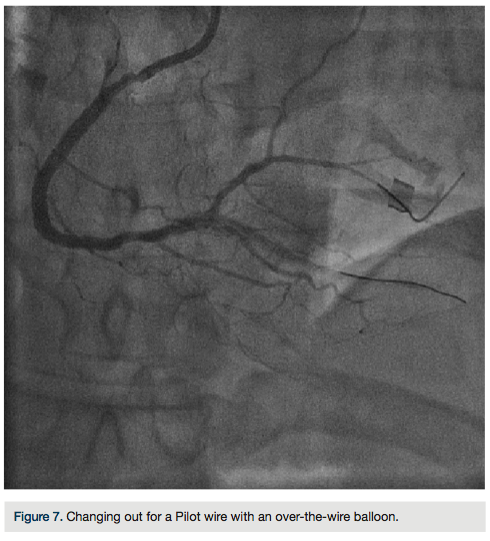

There was transient loss of flow in the posterior left ventricular branch (PLV), which was wired with a Fielder XT wire, and then changed out for a Pilot wire through an over-the-wire balloon (Figure 7). We exchanged for a Runthrough wire into the distal posterior descending coronary artery (PDA). The Corsair was removed from the collateral, and we took the guide and wire from the left system. Two additional 3.0 x 28 mm Promus drug-eluting stents were placed distally prior to the bifurcation. After stent placement, there was good flow in the distal vessel. A gap in between the stents was covered with a 3.0 x 8 mm Promus drug-eluting stent. We then